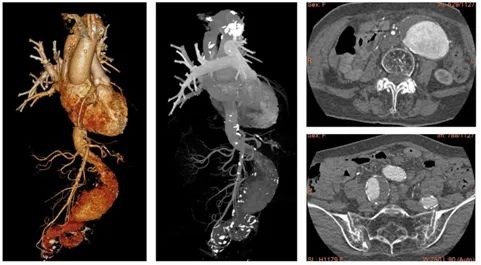

接诊的崔文军主任一触摸腹部,便判断很可能是“腹主动脉瘤”。随后的主动脉CTA检查证实了这一判断——刘奶奶的腹主动脉最粗处直径已达7厘米,一侧髂动脉也扩张至近4厘米,均处于破裂边缘!

▲ 术前胸腹主动脉CTA检查,腹主动脉巨大动脉瘤